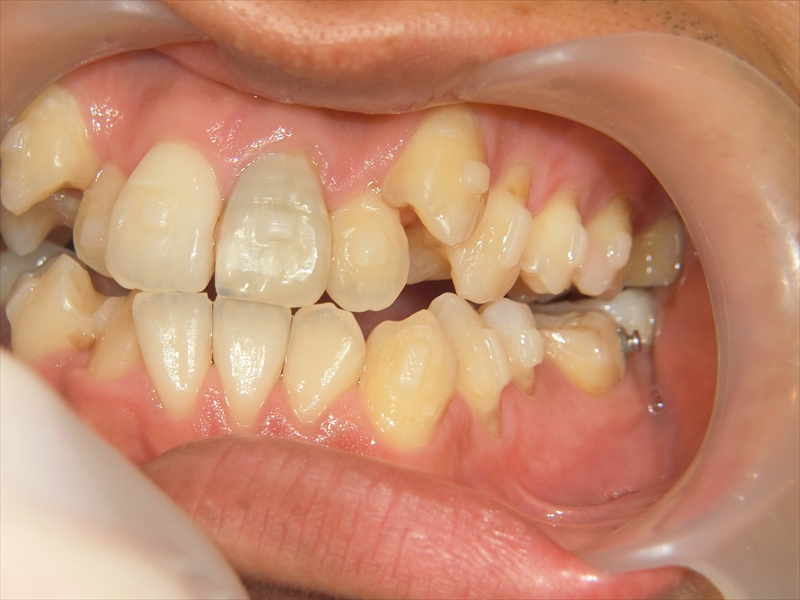

また、歯並び全体がお顔の中心よりも右にずれており、噛み合わせも左右で違っていました。

右側では下の歯が前に出すぎており、左側では逆に下の歯が少し後ろに下がっているという、左右でバランスの取れていない噛み合わせでした。

治療前後 写真